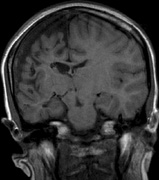

Optic nerve gliomas may involve the optic chiasm and be associated with endocrine disorders or nystagmus.68–70 Surgical excision of chiasmal gliomas (Fig. 6) carries a high risk of visual loss. Invasion of the hypothalamus or the third ventricle carries a poor prognosis, with greater than 50% 15-year mortality rate.71 One review of radiation treatment for chiasmal gliomas collated data from small case series and found no significant long-term improvement in visual function, progression, or mortality with radiation treatment.71 Other reports suggest that radiation doses over 4500cGy improve symptoms and slow progression of chiasmal gliomas over several years.72 Adequate tumor coverage by radiotherapy results in irradiation of normal brain and nearly all children need hormone replacement.73 Chemotherapy is an alternative.74,75

|